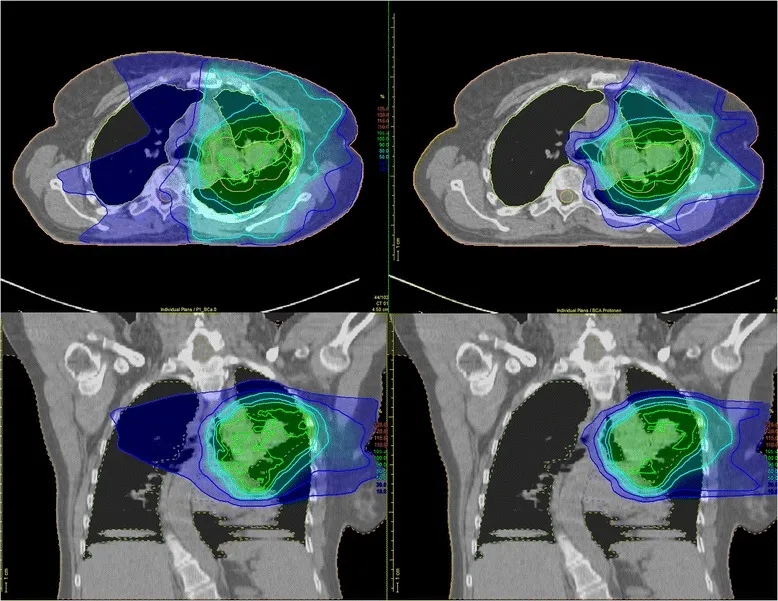

安全性数据表现优异:47例患者(92%)仅出现1级及以下急性肺毒性,仅3例为2级、1例为3级,无4级及以上急性肺毒性发生,且患者远期毒性反应极少。此外,既往研究针对局部晚期NSCLC患者的剂量分布分析也证实了质子治疗的安全性优势——与调强光子放疗(IMRT)相比,质子治疗对危及器官(OAR)的剂量显著更低:传统IMRT易使辐射波及肿瘤周围健康组织(详见下图左),而质子疗法可将大部分辐射精准集中于肿瘤靶区(详见下图右)。

▲图源“Trials”,版权归原作者所有,如无意中侵犯了知识产权,请联系我们删除